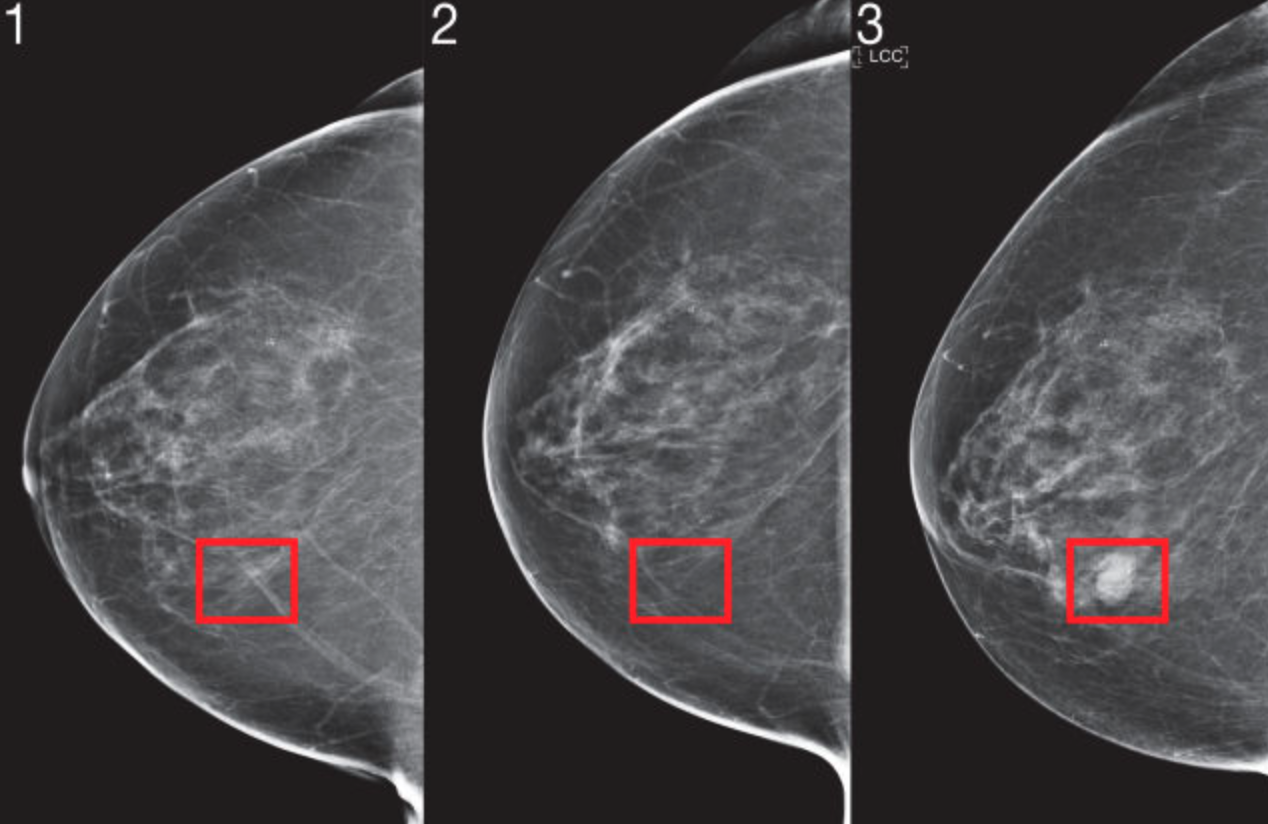

Pesquisadores do MIT liderados pela Clínica Abdul Latif Jameel, através de um sistema de machine learning voltado para saúde, fez um treinamento a partide 200.000 exames para otimizar sua base de dados para melhores acertos. O algoritmo consegue prever para qualquer etinia, gênero ou raça. A prioridade inicial seria para câncer de mama, porém facilmente evoluirá para outros tipos. A idéia da iniciativa é colocar o sistema de análise como padrão para todos os exames iniciais. Pois mesmo com toda tecnologia, os mamogramas ainda tem a mesma qualidade de 60 anos atrás, e essa facilidade adicional de diagnóstico pode melhores exponencialmente esse diagnóstico precoce. Essa já é uma iteração ainda mais revolucionária aos sistemas já existentes de IA para tratamentos de imagem. Você coloca diversos parêmetros que aumentam ainda mais a precisão e com isso possa ser oferecido um tratamento mais correto e rápido.